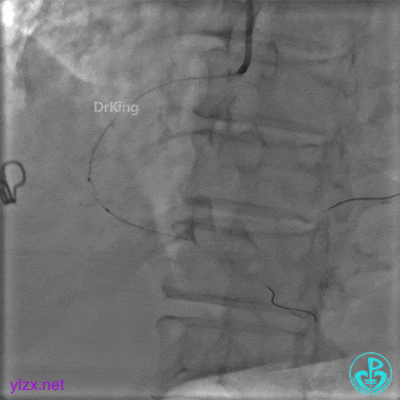

更换6F JR 4.0指引导管,Runthrough NS进入PL分支。

2.0×15mm球囊扩张PL分支开口后PL恢复2级血流。

PL远端血管周围似乎有片状造影剂滞留。

经微导管PL分支造影,该如何解读这个经微导管造影结果?

经指引导管造影。

经微导管造影。